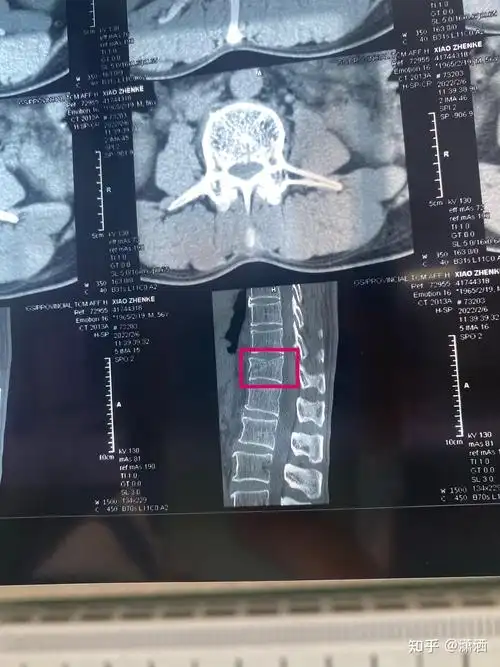

病例分享:胸12椎体压缩性骨折

胸椎(t12)压缩性骨折治疗记录 - 知乎